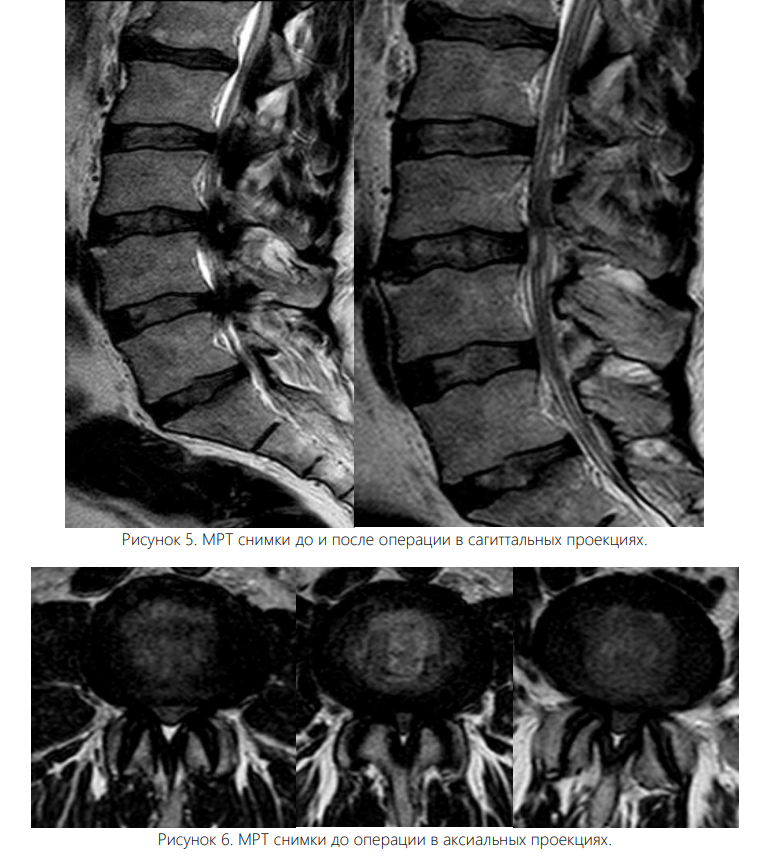

Вмешательство осуществляли под интубационным наркозом. Все операции были выполнены одним и тем же хирургом. Пациента укладывали на живот с подложенными мягкими валиками под грудной клеткой и тазом, уменьшая таким образом внутрибрюшное давление и степень интраоперационного кровотечения. Уровень вмешательства определяли с помощью интраоперационных флюороскопии. Срединный кожный разрез длиной 0,7 см располагался точно над уровнем соответствующего межпозвонкового диска. Зона ламинотомии в краниальном направлении простиралась до области прикрепления желтой связки к дуге вышележащего позвонка, а каудально резекция дуги нижележащего позвонка составляла не более 2-3 мм для адекватного обнажения ножки позвонка. Проведен анализ результатов хирургического лечения 102 больных со стенозом поясничного отдела позвоночника, находившихся в отделении вертебрологии Республиканском центре травматологии и ортопедии Узбекистана в период с 2020 по 2024 год. Для определения размера позвоночного канала, а также степени дегенеративного стеноза в позвоночный канал всем больным была выполнена рентгенография, МСКТ, МРТ. Возраст больных от 44 до 84 лет, мужчин – 46%, женщин – 54%. Всем пациентам была произведена операция - эндоскопическая декомпрессия методом PSLD (Posterior Spinal Lumbar Decompression). На одном уровне (44 больных) и (32 больных) – на двух уровнях, 18-больных в трех уровнях, 8-больных в четырех уровнях.

Увеличение площади поперечного сечения дурального мешка и клинически значимое уменьшение боли в спине и нижних конечностях получено в обеих группах пациентов. В раннем послеоперационном периоде болевой синдром в нижних конечностях и спине оказался менее выраженным в эндоскопической группе, что связано с меньшей хирургической травмой мягких тканей.

Доля хирургических осложнений при эндоскопической декомпрессии составила 9,8 %, тогда как при микрохирургических операциях - 4,2 %. Перфорация дурального мешка при эндоcкопической декомпрессии, потребовавшая ушивания дефекта с конверсией операции в открытую, имела место при освоении методики, с 2021 г. не встречается. В литературе частота осложнений в группах микрохирургической и эндоскопической декомпрессии была схожей. Стеноз межпозвонкового отверстия и корешкового канала наблюдался у 62 больных, а в 40 случаях установлен диагноз - стеноз центрального канала.